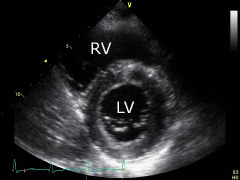

Name the view

short axis

What is wrong here

Left ventricle hypertrophy